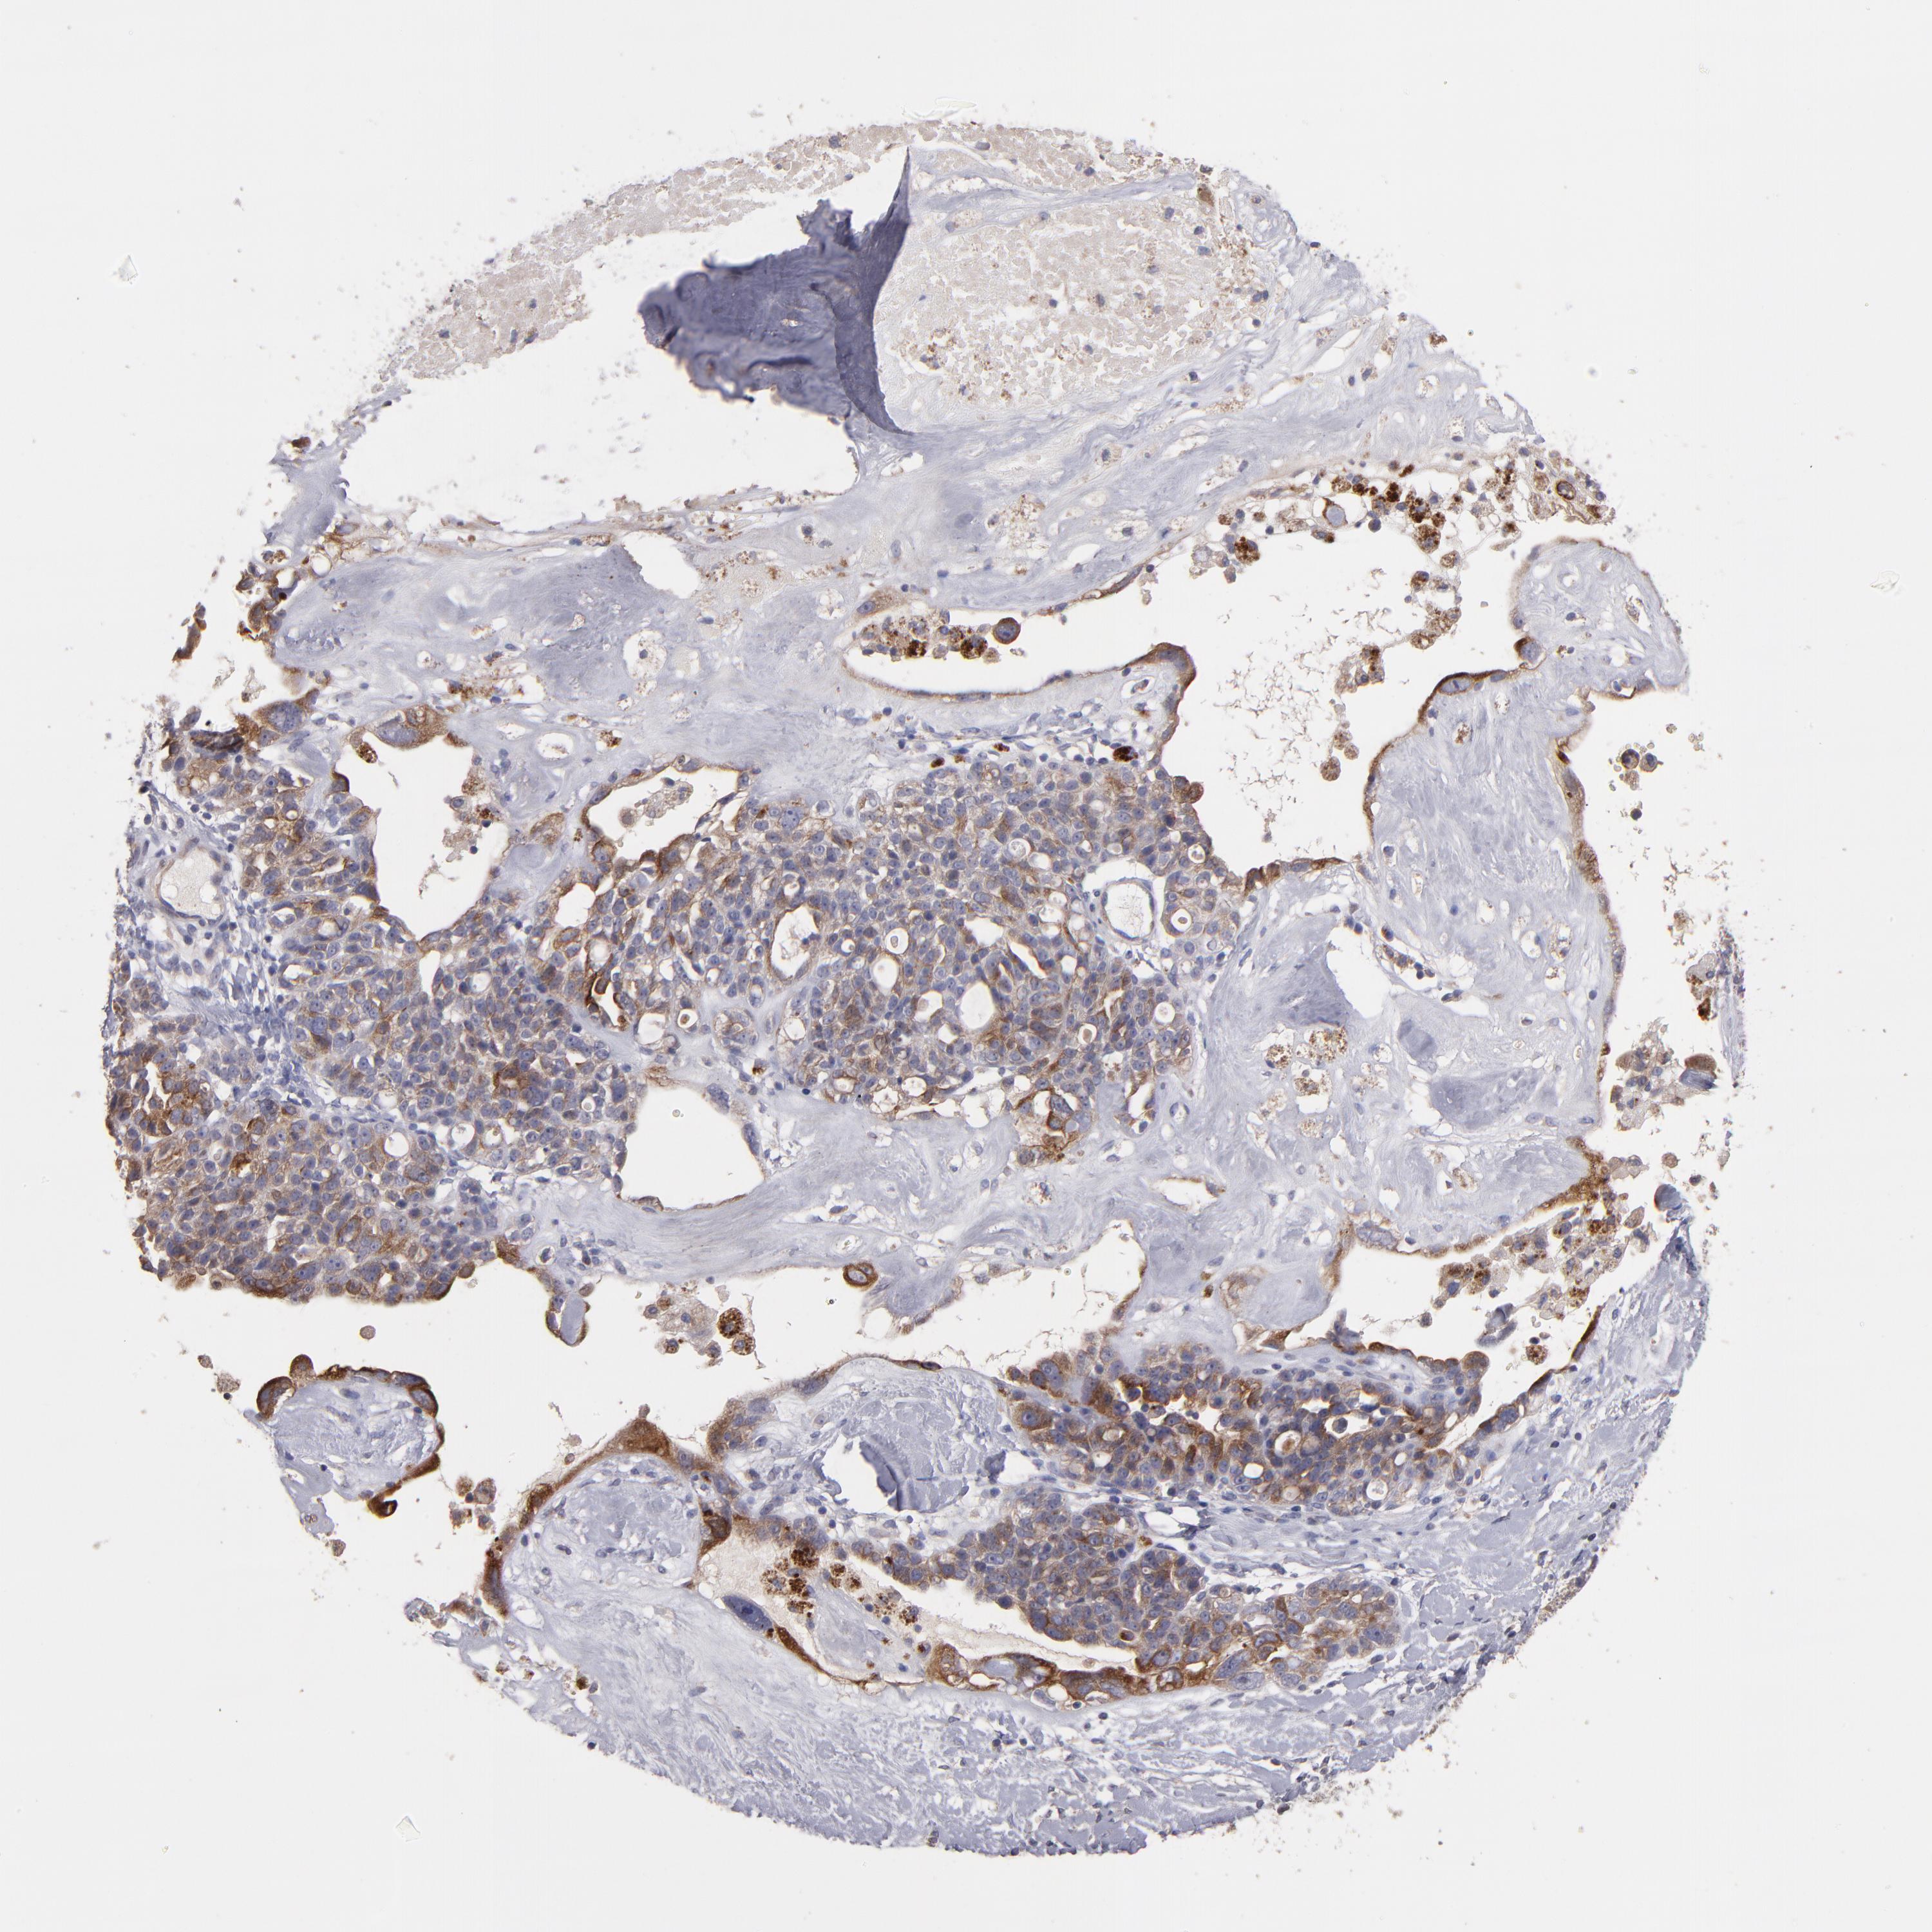

OVARIAN CANCER - Protein expressioni

A mouse-over function shows sample information and annotation data. Click on an image to view it in a full screen mode. Samples can be filtered based on level of antibody staining by selecting one or several of the following categories: high, medium, low and not detected. The assay and annotation is described here.

Note that samples used for immunohistochemistry by the Human Protein Atlas do not correspond to samples in the TCGA dataset.

Antibody stainingi

Antibody staining in the annotated cell types in the current human tissue is reported as not detected, low, medium, or high, based on conventional immunohistochemistry profiling in selected tissues. This score is based on the combination of the staining intensity and fraction of stained cells.

Each image is clickable and will lead to virtual microscopy that enables deeper exploration of all samples and also displays staining intensity scores, fraction scores and subcellular localization as well as patient and tissue information for each sample.

Antibody HPA003047

Staining

High

Medium

Low

Not detected

Intensity

Strong

Moderate

Weak

Negative

Quantity

>75%

75%-25%

<25%

None

Location

Nuclear

Cytoplasmic/membranous

Cytoplasmic/membranous,nuclear

Cystadenocarcinoma, serous, NOS

Cystadenocarcinoma, mucinous, NOS

Carcinoma, endometroid